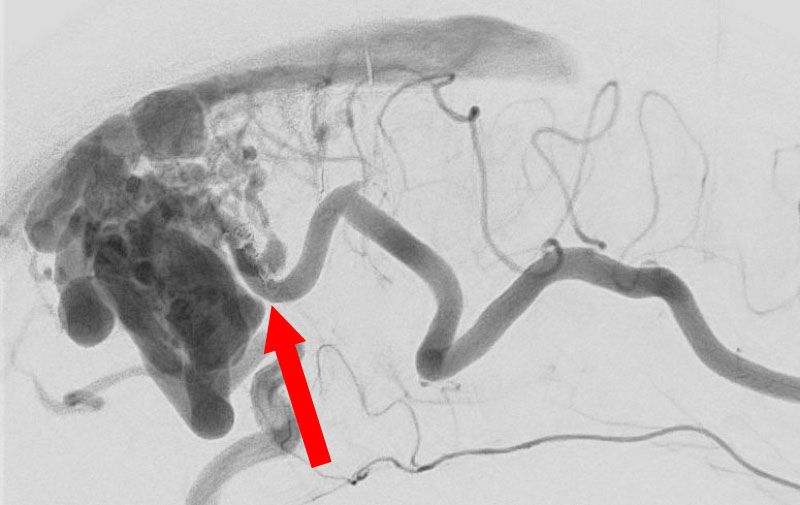

'25年10月

硬膜動静脈瘻

50代

救急外来

No.1591 手術前